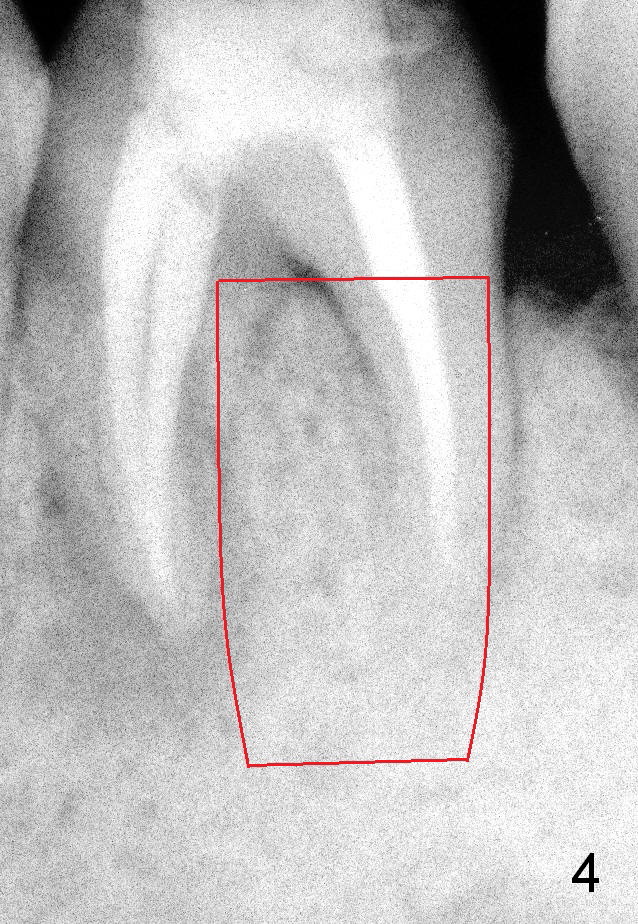

Where to place the immediate implant, septum (Fig.3), mesial or distal (Fig.4) socket? What is rationale?